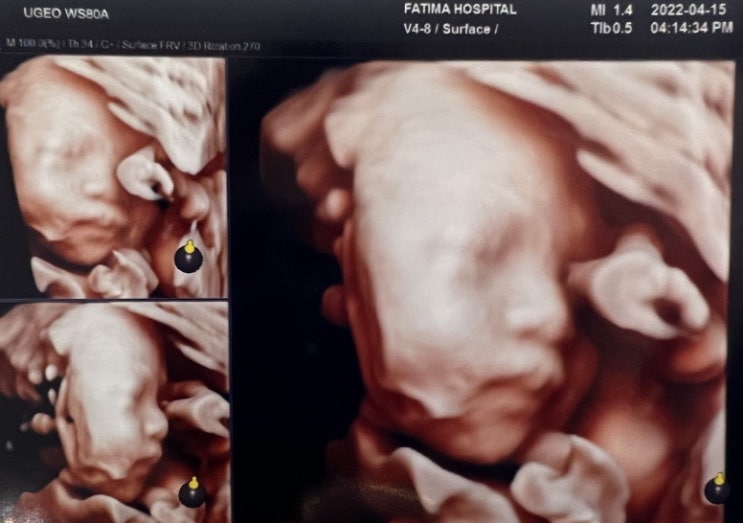

임신기록 8. 임신8개월(28주-31주): 입체초음파, 태교여행, 아기침대 구입(보니 유아침대), 8개월차 증상

진료기록 1 또또와 함께 엄마도 자라고 있어 태아 BPD(머리둘레): 7.68cm AC(복부둘레): 24.97cm FL...